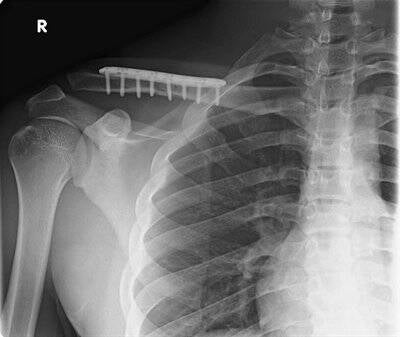

Als de breuk teveel verplaatst is of uit teveel fragmenten bestaat, zal er meestal een operatieve behandeling nodig zijn. Hierbij wordt de breuk terug op zijn plaats gezet en gestabiliseerd door middel van een plaat en schroeven.

Clavicula fractuur

Operatieve behandeling met plaat en schroeven